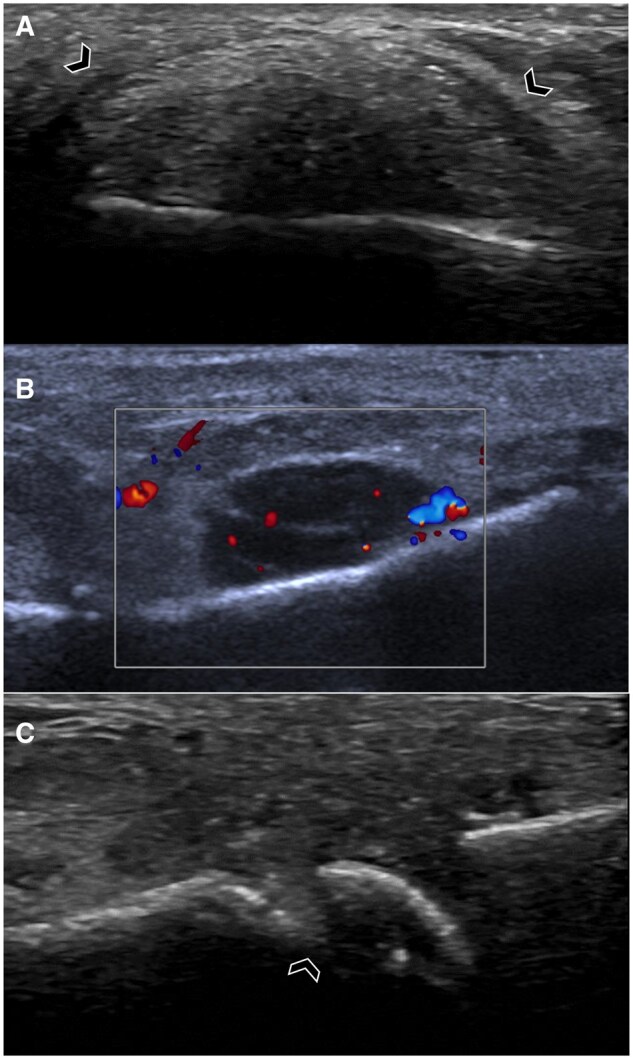

痛风是一种常见的全身性疾病,由尿酸钠(MSU)晶体沉积在关节和关节周围结构,导致反复发作的炎症。当晶体吸吸不可行、临床诊断不确定时,影像学对确定诊断有重要作用。每种成像方式都有其独特的作用。x光片可以显示痛风后期的特征性侵蚀和痛风。超声在痛风的诊断和评估中起着重要作用。双能计算机断层扫描(DECT)可以精确地显示MSU沉积物,并可以确定疾病负担。MRI可以评估非特异性炎症和结构改变。超声和DECT都被强调为诊断算法的一部分,随着最近的进展和证据,成像的作用正在扩大。这篇综述提供了一个以成像为中心的每一种模式的概述及其在痛风中的发展意义。

Gout is a common systemic disease defined by deposition of monosodium urate (MSU) crystals in articular and peri-articular structures, leading to recurrent bouts of inflammation. Imaging plays an important role in establishing the diagnosis when crystal aspiration is not feasible and the clinical diagnosis is uncertain. Each imaging modality has a unique role. Radiographs can demonstrate characteristic erosions and tophi in later stages of gout. Ultrasound has a major role in the diagnosis and assessment of gout. Dual-energy computed tomography (DECT) enables precise visualization of MSU deposits and can determine disease burden. MRI can assess for non-specific inflammatory and structural changes. Both ultrasound and DECT are emphasized as part of diagnostic algorithms and the role of imaging is expanding with more recent advancements and evidence. This review provides an imaging-centric overview of each modality and its evolving significance in gout.